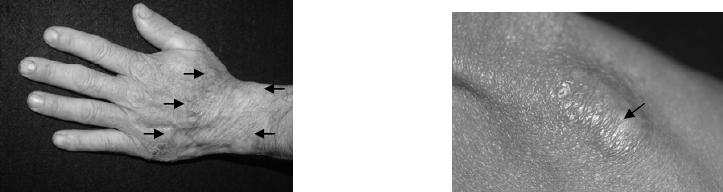

Figura 12: Exemplo de lesão plana (seta).

Figura 13: Exemplos de Lesões elevadas (setas).

Figura 14: Extensa lesão plana (limitada pelas setas). Figura 15: Detalhe de lesão plana (seta).